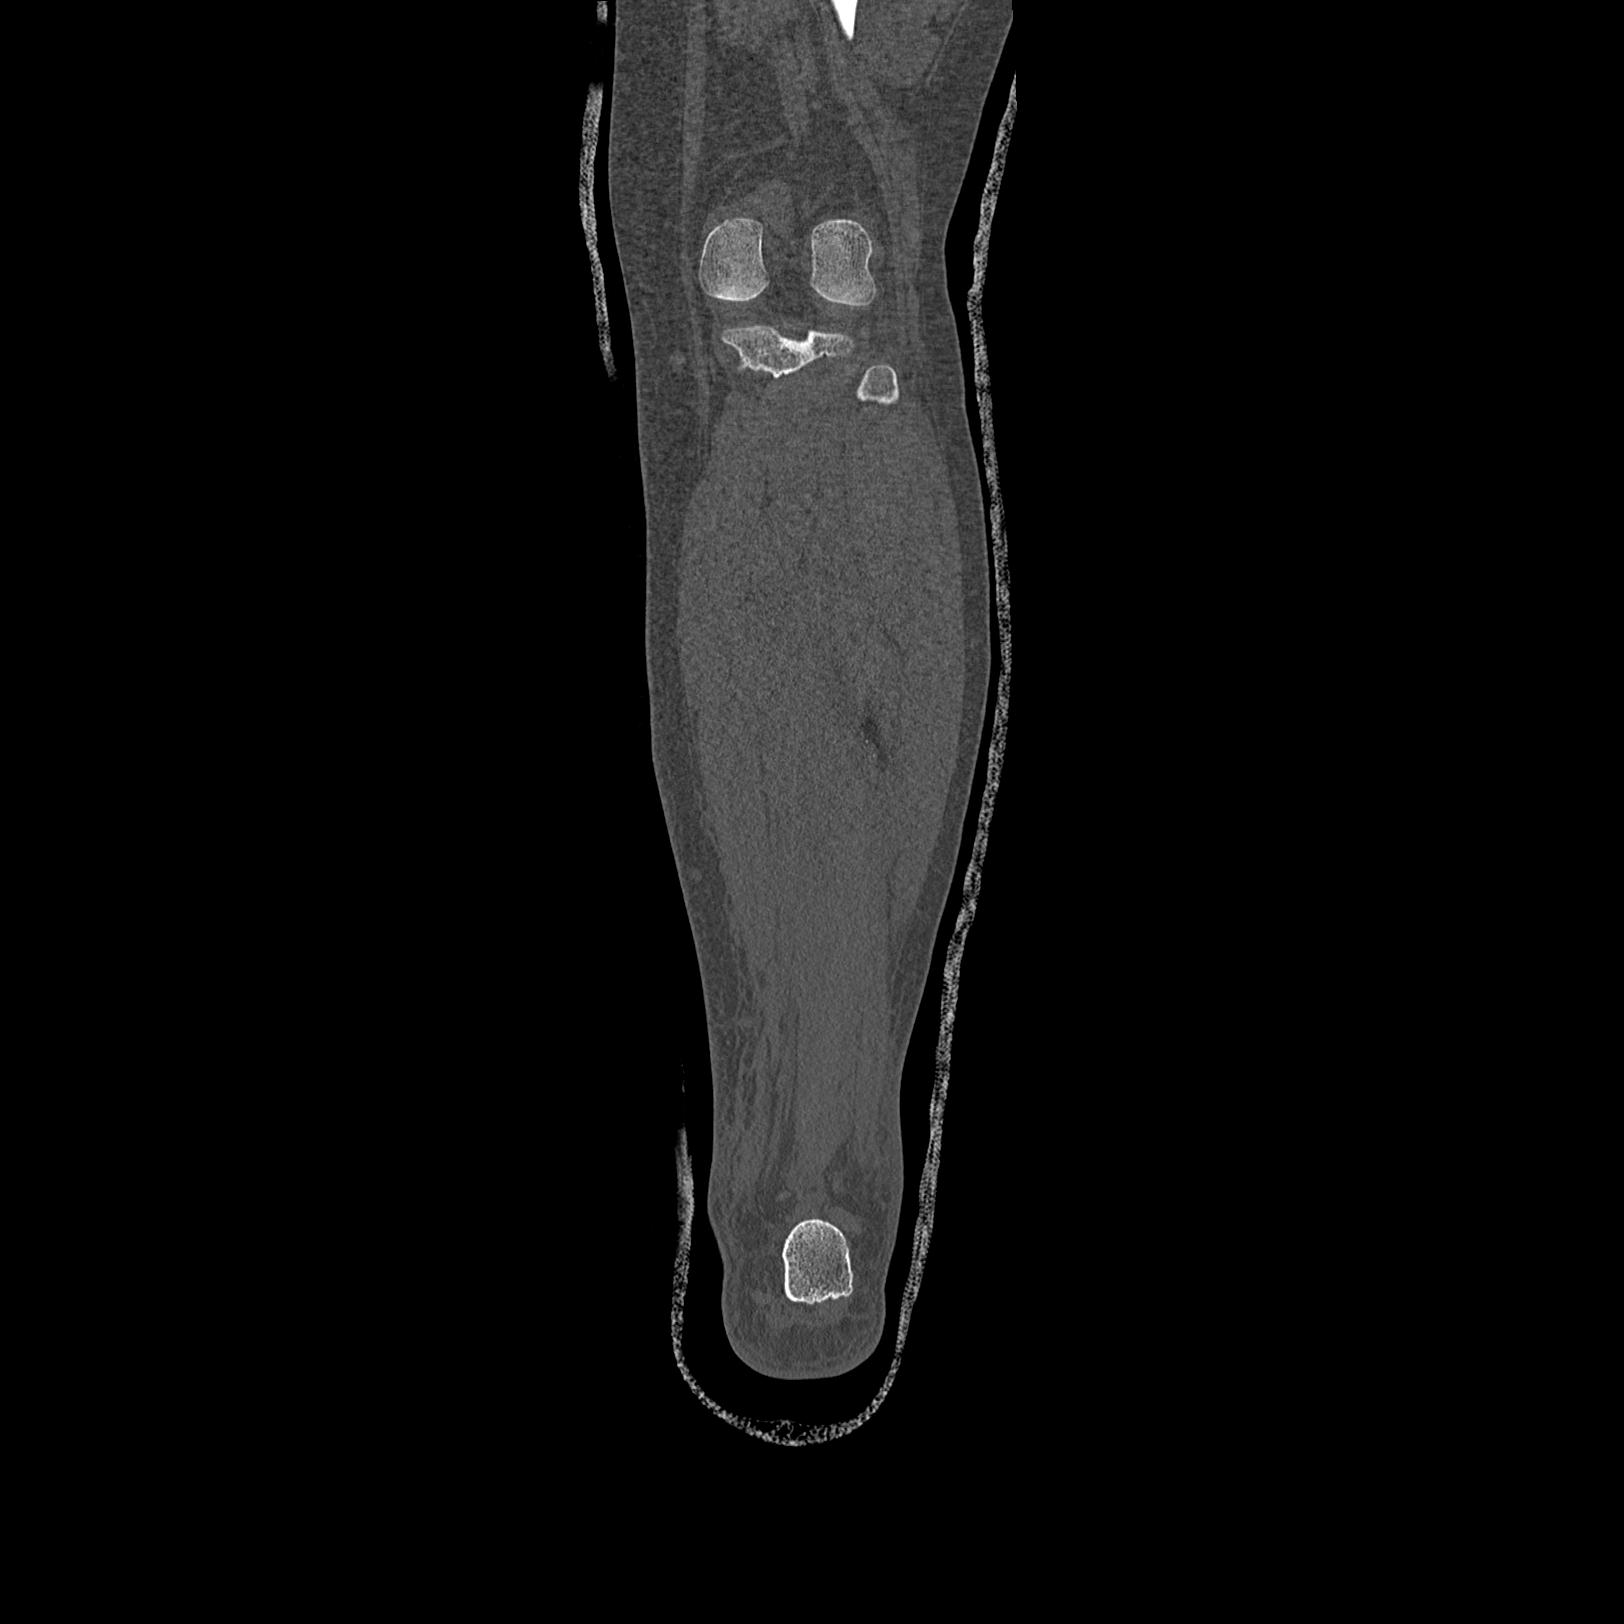

102803 1/12(キウスなし) 1/27 左下腿 4R 30歳女性 左脛骨軸内釘